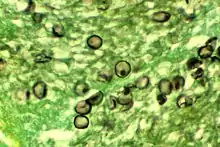

| P. jirovecii cysts in tissue | |